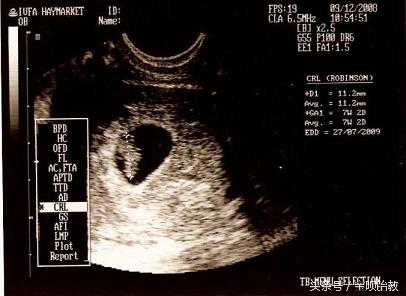

言归正传,看B超的胎囊就可以猜男女,那么胎囊到底是什么呢?

胎囊,也叫孕囊,是怀孕最初胚胎的形态。

如何正确的胎囊看男女?

2、看形状:

像茄子或长条状的是男宝宝可能性大,圆圆的是女宝宝可能性大。

孕囊都是圆柱状的,每个B超师做B超的时候,截面会截取的方位不一样,有的横截面,有的截取竖截面,所以,看图片是长的还是圆的,不能判断男女。所以看数据的时候,数据一定要有3个。

3、看数据:

如果B超师取了40*20的截面,貌似男孩的数据,结果生出了闺女,就会造成孕囊看男女不准的说法。

所以这里一定要是3个数据。如果长和宽的相差在一倍以上男宝宝可能性大。长和宽相等女宝宝可能 性大。

如果孕囊成等差数列,比如40*30*20,这样就是女孩, 有3个数据最好判断,两个数据差不多,第三个数据比前两个小一倍,那肯定是儿子,如果成递减数据就是女儿。